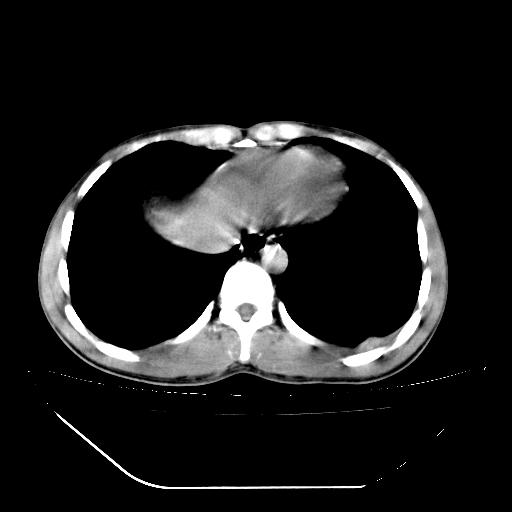

m-25y 高空堕落 12 月5号

12月7号病人尿量200ml/24h 急查双肾ct

左肾挫裂伤并肾周血肿;

肝肾间隙可见液区,建议手术探查;